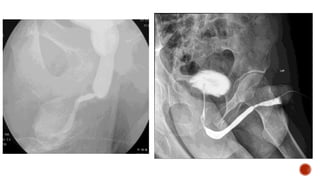

 It isthe roentgenographic demonstration of urethra by the retrograde injection of radio- opaque material through the urethra.

 Strictures Urethral tears Congenitalabnormalities Periurethral or prostatic abscess Fistulae or false passages.

Main indications 1. Traumato urethra. 2. Urethral stricture. 3. Suspected urethral diverticula. Other indications 1. UTI. 2. Reflux nephropathy prior to renal transplant of one/both kidneys. 3. Follow up of patients with spinal cord injury.